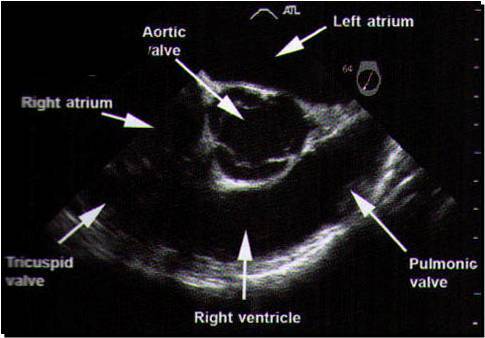

This is looking down to aortic valve